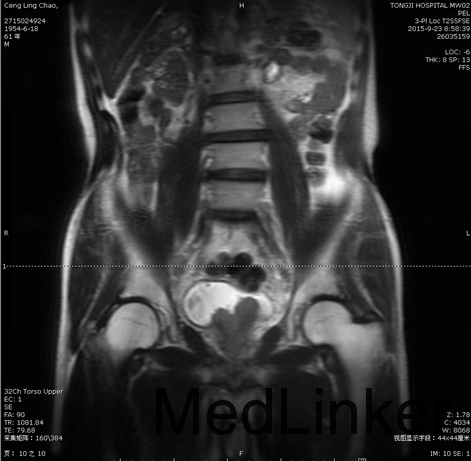

随访:磁共振:膀胱肿瘤术后;膀胱三角区肿瘤性病变,侵犯前列腺、精囊可能; 双侧盆壁及双侧腹股沟淋巴结增多、增大。 病检结果示高级别尿路上皮癌前列腺来源可能性大。建议行进一步检查。 随访磁共振:膀胱肿瘤术后;膀胱三角区肿瘤性病变,侵犯前列腺、精囊可能; 双侧盆壁及双侧腹股沟淋巴结增多、增大。